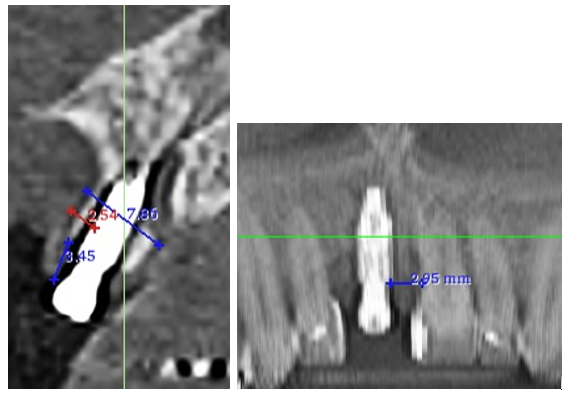

Região do elemento 11 edêntula. Foi realizado o planejamento para instalação de um implante na região desdentada, tentando deixar o mais parecido com o dente vizinho. Após exames complementares e planejamento, foi realizada a instalação de um implante Cone Morse 3.5×10 mm com enxerto Lumina Bone na região vestibular.